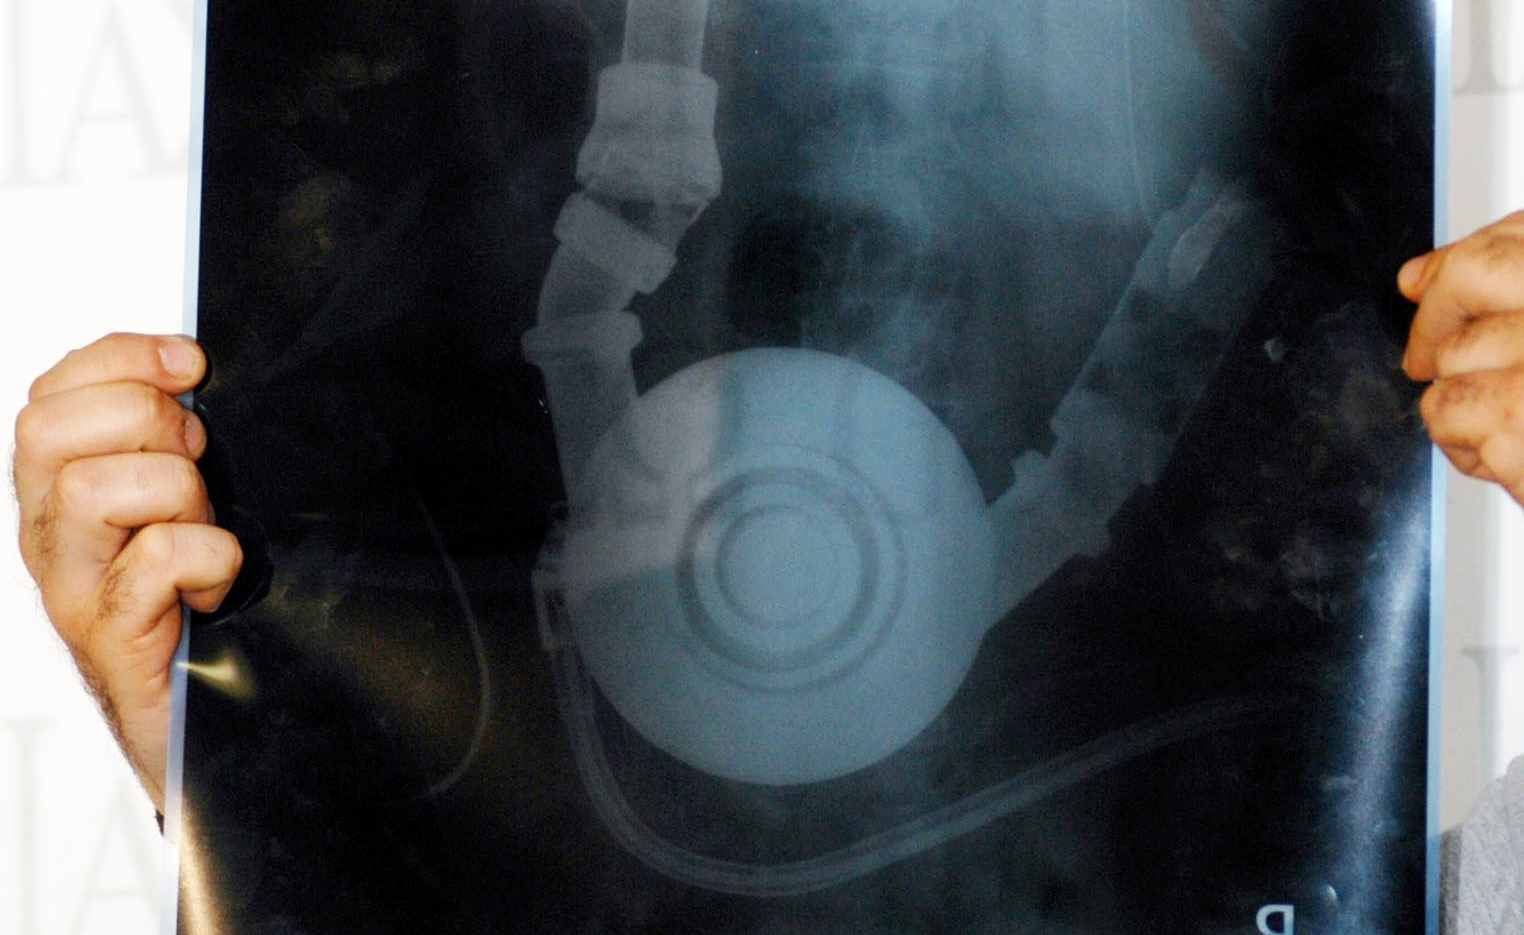

Πρόκειται για ένα περιστατικό που συνέβη στο νοσοκομείο του Ρίου. Σύμφωνα με το dete.gr, εργαζόμενος επισκέφθηκε το Ακτινολογικό Τμήμα προκειμένου να κάνει ακτινογραφία καθώς είχε πρόβλημα στο ένα του άκρο και τότε άκουσε έκπληκτος τον γιατρό να τον ρωτά αν διαθέτει κινητό τηλέφωνο τελευταίας τεχνολογίας!

«Έχω» απάντησε ο ασθενής και εργαζόμενος του Νοσοκομειακού ιδρύματος ! «Ε, τότε» του απαντά ο γιατρός «τράβα μια φωτογραφία και πήγαινέ την στον ορθοπεδικό»!

Ο ασθενής κοιτούσε έκπληκτος τον γιατρό που συνέχισε: «Μην με κοιτάς έτσι, έχει χαλάσει το μηχάνημα που βγάζει τις ακτίνες η μόνη λύση να εξυπηρετηθείς είναι αυτή»!